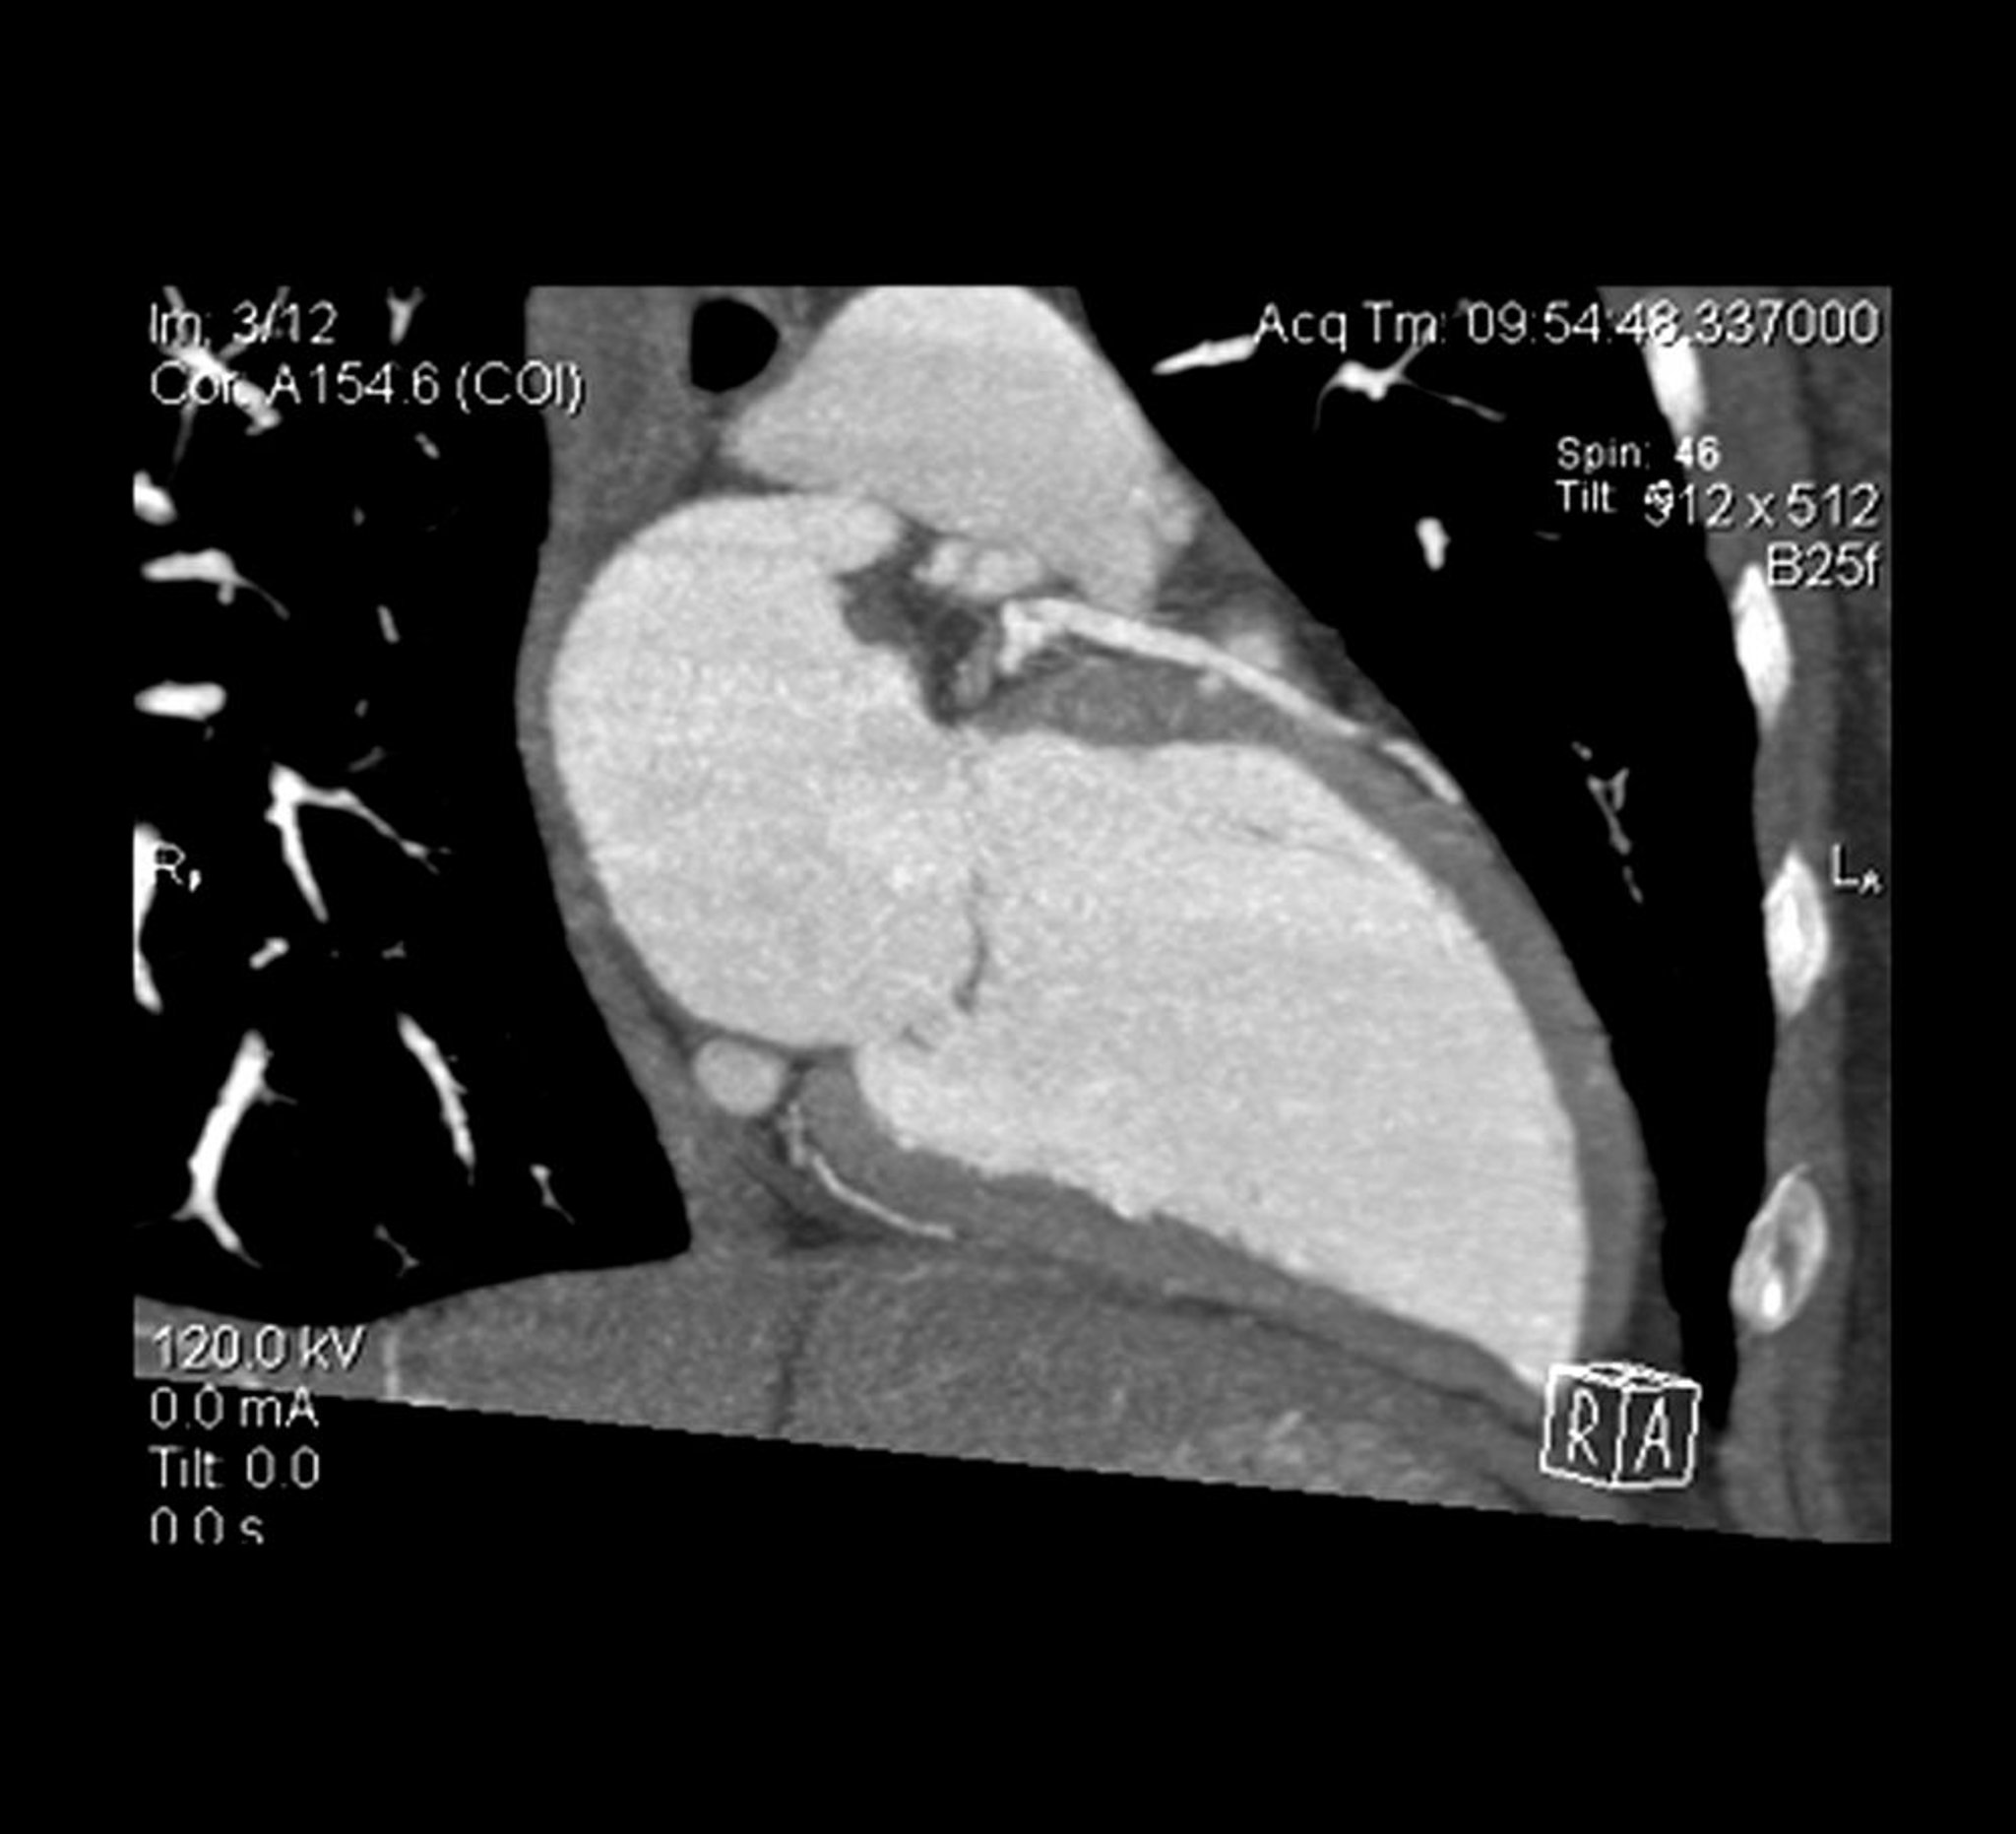

AngioTDM cardiaque

Vue en coupe transversale d'une angio-TDM cardiaque qui montre le ventricule gauche et l'artère interventriculaire antérieure gauche.